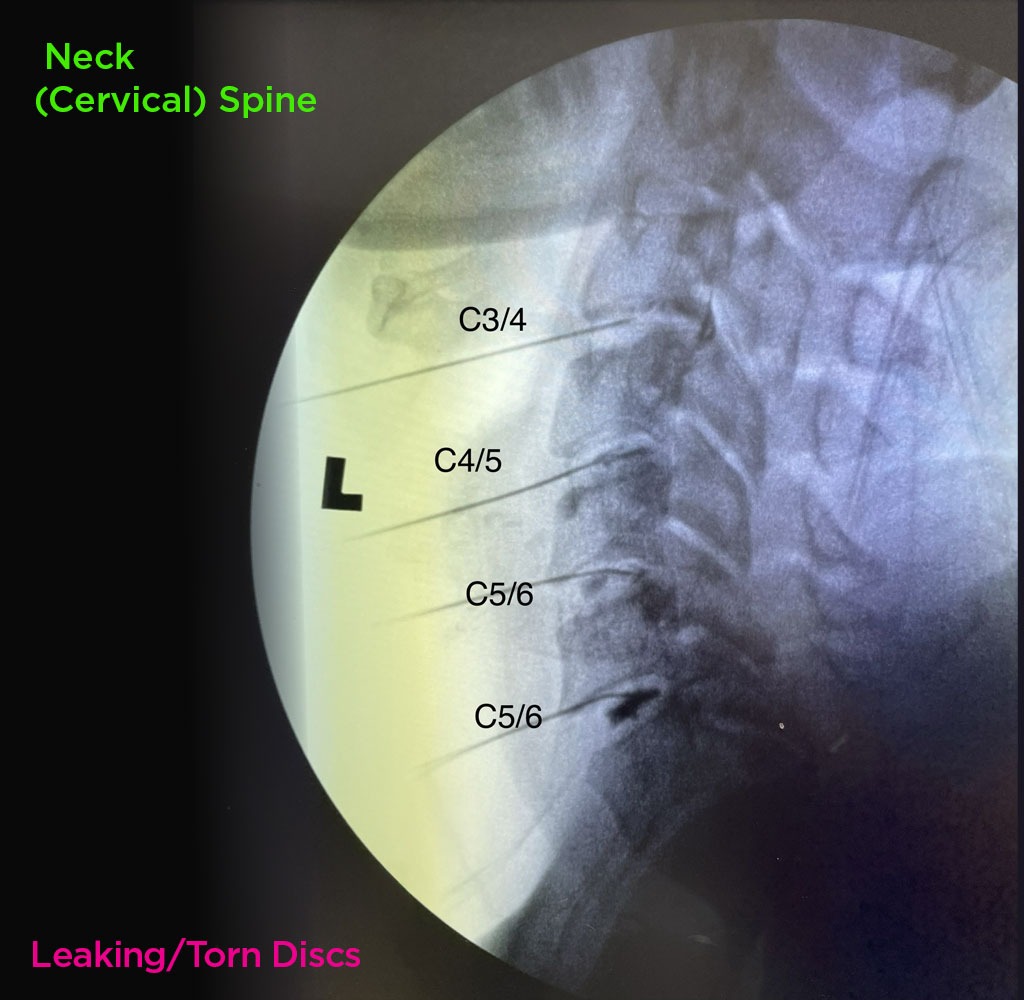

Annulargram™ Gallery

This gallery contains Annulargram images.

The Annulargram is a pain-free test and a crucial part of the DISCSEEL Procedure that identifies even the most subtle tears in spinal discs that MRI and discography cannot.

During the Annulargram, every disc in the region is tested to address current and future pain issues by finding even the most subtle annular tears. With the Annulargram, damaged spinal discs are pinpointed and precisely treated with Fibrin, leaving all healthy discs as they are.